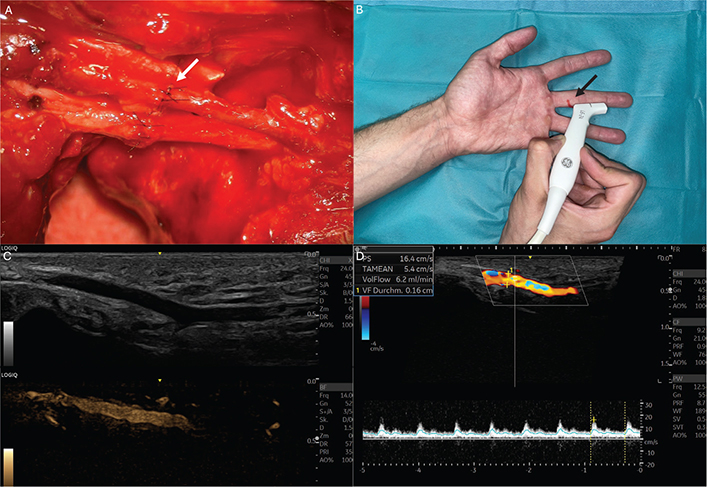

All examinations were performed by a single experienced investigator under standardized conditions. To minimize physiologic fluctuations in digital blood flow, all participants underwent an acclimatization period of 20 min at constant room temperature prior to the examination. Examinations were conducted with the patient in a seated position, with both hands supported at heart level on an examination table. Prior to sonographic assessment, finger length was measured from the metacarpophalangeal joint to the fingertip. Patency and anterograde flow of the reconstructed digital artery were assessed using Allen test and duplex ultrasonography (Figure 1). Duplex ultrasonography was performed using GE HealthCare’s LOGIQ™ E10 series with a high-frequency linear L6–24 MHz transducer using a manufacturer-provided preset for finger examination. Standard B-mode imaging was combined with color Doppler and pulsed-wave Doppler ultrasound to assess vessel morphology, patency, flow direction, and flow velocity. Anterograde arterial blood flow distal to the anastomosis was confirmed using color Doppler imaging and spectral Doppler waveforms. Volume flow was calculated based on time-averaged mean velocity and vessel diameter measurements obtained in longitudinal section. Anterograde blood flow in the reconstructed artery was compared with the contralateral artery of the injured digit and with the corresponding finger of the uninjured hand.

Figure 1. Images of a representative patient with unilateral digital artery repair included in this study. (A) Image showing microsurgical anastomosis of a unilateral digital artery (white arrow) (B) Clinical scenario of duplex ultrasound examination measuring signals distal to the vascular anastomosis. The height of injury and anastomosis is marked in red (black arrow). (C) Ultrasound images showing digital artery in B and M Mode. (D) Duplex sonography of digital artery measuring diameter, peak systole (PS) and volume flow (VolFlow).